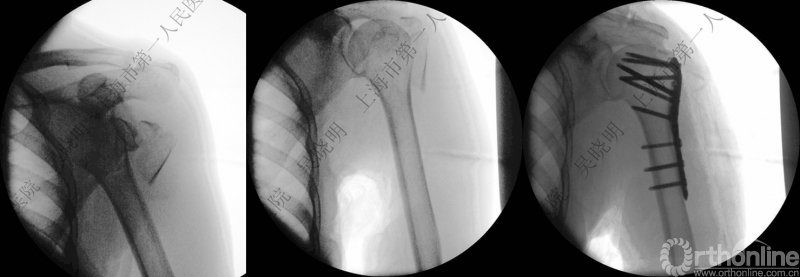

外翻压缩型肱骨近端骨折

钢板固定

全麻下闭合复位,钢板固定